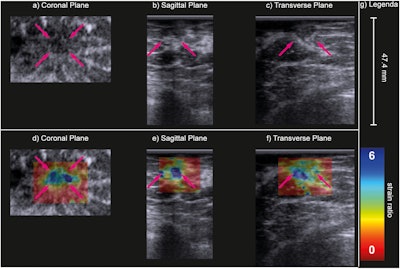

B-mode (a–c) and strain ratio (d–f) images of a carcinoma of unknown type in the coronal (a, d), sagittal (b, e) and transverse (c, f) planes. In the strain images (d–f), the maximal principal strain ratios are superimposed on the B-mode images of the top row. The purple arrows indicate the lesion. Image courtesy of Ultrasound in Medicine & Biology. Image available for fair use under creative commons license.

Adding 3D elastography to the automated scanning protocol showed a significant difference between malignant and benign lesions. On maximal principal strain, the median strain ratio was 1.7 in malignant lesions, with a range between 1.0 and 3.2. Benign lesions meanwhile had a median strain ratio of 1.0, with a range between 0.6 and 1.9 (p = 0.007).

The team also found no significant difference in strain ratios between malignant and benign lesions when it came to using axial strain ratio. This included a median ratio of 0.8 for malignant lesions and 0.6 for benign lesions.